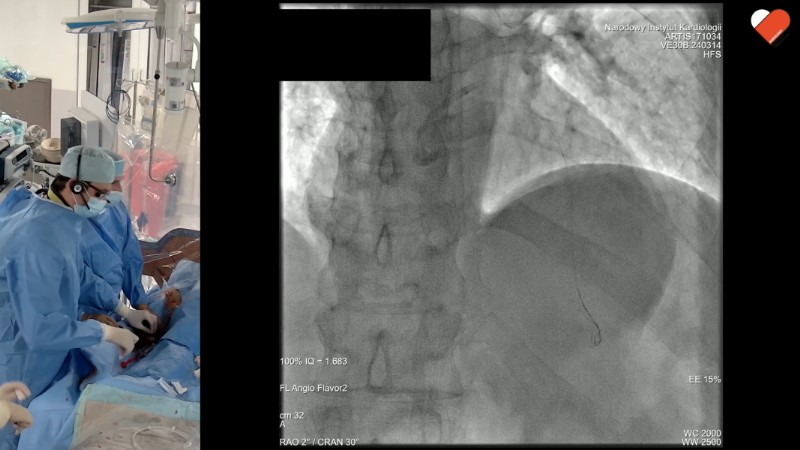

Integration of CT and IVUS for treatment of coronary artery disease in daily practice: from planning to drug-eluting therapy

This EuroPCR 2025 session highlights how imaging can drive precision in modern PCI. From CT-guided planning to IVUS-guided drug-eluting balloon interventions, each presentation offers practical insights into optimising patient outcomes. Step-by-step approaches and recorded cases illustrate how to tailor tool and technique selection, while also addressing how to best integrate imaging into the use of drug-eluting therapies.